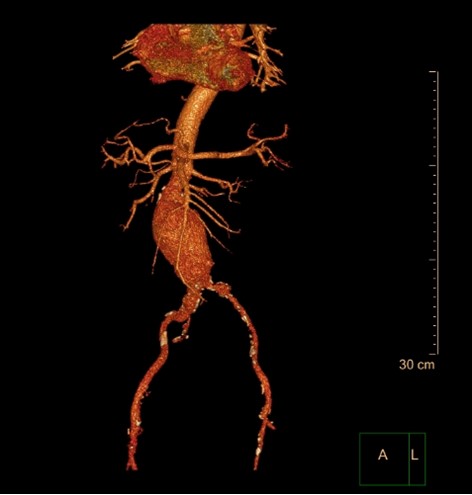

A 56-year-old Caucasian male, with prior history of chronic obstructive pulmonary disease and nicotine dependence presented to the hospital with shortness of breath, productive cough, with fever and chills. He was found to be in acute exacerbation secondary to right basilar pneumonia and initiated on treatment. As part of the initial workup, computerized tomography (CT) scan of the chest and abdomen was also ordered, which revealed an incidental finding of an infrarenal abdominal aortic aneurysm, measuring 5.1 x 5.1cm x 10.4cm. Blood cultures ordered on admission returned positive for Salmonella enteritidis, which was sensitive to ceftriaxone, and appropriate antibiotic treatment was initiated.

The patient subsequently began to develop abdominal discomfort and new fever spikes. Repeat lab findings showed an increased leukocyte count, and CT angiogram demonstrated a significantly increased size to 7.6 x 9.1 x 13.3cm, concerning for impending rupture and underlying aortitis. Nuclear white blood cell scan was performed and revealed abnormal increased uptake involving the mid and distal abdominal aorta, suggestive of infection. Vascular consultation was obtained, and he successfully underwent percutaneous endovascular aortic repair. He tolerated the surgery well and observed improvement in symptoms, following which he was discharged.

Image 2: 3D Reconstruction of CT of Abdominal Aortic Aneurysm.